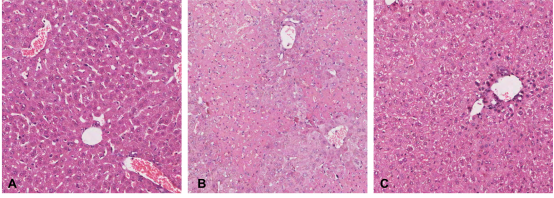

鄧志華課題組查閱大量文獻(xiàn)資料,發(fā)現(xiàn)肝星狀細(xì)胞(HSC)在肝纖維化中發(fā)揮關(guān)鍵作用,此外近年研究還發(fā)現(xiàn)HSC具有免疫細(xì)胞特征,直接參與肝臟的免疫調(diào)控,但由于HSC是肝臟的非實(shí)質(zhì)細(xì)胞,數(shù)量極少,分離小鼠原代HSC非常困難,限制了其研究進(jìn)展。課題組經(jīng)過(guò)不斷摸索研究,運(yùn)用OptiPrep分離液結(jié)合原位手工灌注法分離到BALB/c小鼠高純度高得率的原代HSC,倒置熒光顯微鏡下觀察:新分離的HSC呈圓形,具有豐富的脂滴,在328nm波長(zhǎng)的紫外光激發(fā)下自發(fā)藍(lán)綠色熒光,逐漸從圓形變?yōu)樗笮位蛐切?,培養(yǎng)7d后,伸出細(xì)長(zhǎng)的偽足。原代HSC油紅O染色陽(yáng)性,胞漿中的脂滴呈紅色,細(xì)胞核呈藍(lán)色,傳2代后免疫細(xì)胞化學(xué)染色HSC完全表達(dá)α-SMA和Desmin,自發(fā)活化。課題組進(jìn)一步將BALB/c來(lái)源的HSC與C57BL/6小鼠脾臟來(lái)源的Treg細(xì)胞共培養(yǎng),觀察HSC對(duì)Treg的誘導(dǎo)作用,異體活化的HSC可在體外呈劑量依賴(lài)性、通過(guò)細(xì)胞-細(xì)胞直接接觸方式誘導(dǎo)Treg增殖,擴(kuò)增的Treg可有效表達(dá)FoxP3,在體外可有效抑制Teff細(xì)胞增殖。為進(jìn)一步證實(shí)擴(kuò)增的Treg的免疫調(diào)節(jié)活性,將擴(kuò)增的Treg通過(guò)尾靜脈注射到ConA誘導(dǎo)的AIH小鼠體內(nèi),觀察其對(duì)AIH小鼠受損肝臟的影響,發(fā)現(xiàn)擴(kuò)增的Treg可調(diào)節(jié)AIH小鼠脾臟Treg/Th17比例失衡,肝臟炎癥和肝細(xì)胞壞死明顯減輕[圖2],血清ALT、AST水平IL-6、TNFα、IFN-γ水平降低,發(fā)揮了良好的治療作用。該課題為尋找替代糖皮質(zhì)激素/硫唑嘌呤治療AIH的免疫細(xì)胞療法提供了可靠的實(shí)驗(yàn)研究結(jié)果。

圖2過(guò)繼轉(zhuǎn)移體外擴(kuò)增的Treg細(xì)胞后AIH模型小鼠肝臟病理變化(A:正常肝臟B:AIH模型肝臟C:過(guò)繼轉(zhuǎn)移Treg后肝臟)